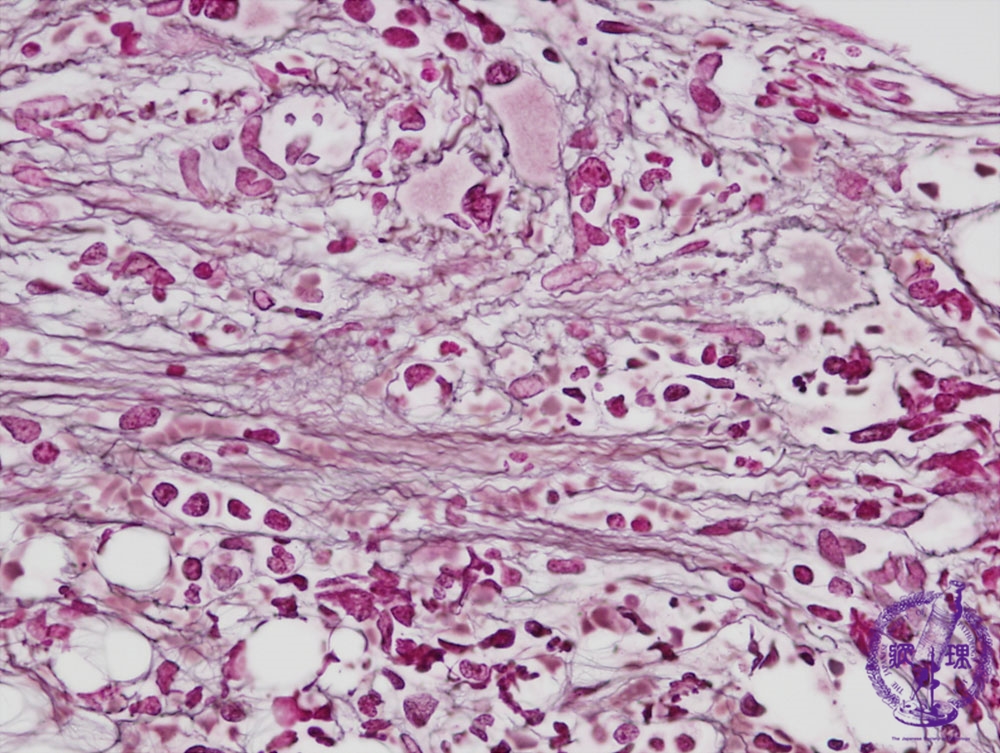

Microscopic image (reticulin stain, high power view): Black reticulin fibers are conspicuous in contrast with the normal marrow which rarely contains reticulin fibers.